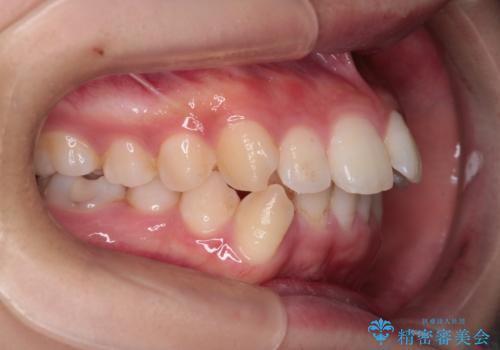

- 前歯から奥歯にかけて歯の重なりが激しい歯のがたつき(重度叢生)を主訴にご来院されました。精密検査の結果、歯が並ぶスペースが大幅に不足しており、歯並びを整え、口元を美しく引っ込めるためには、スペースの確保が必要と診断しました。そこで、上下左右の第一小臼歯(4番目の歯)を計4本抜歯し、そのスペースを利用して歯並び全体を整える抜歯矯正の治療計画を立案。装置には、透明で目立たないインビザラインを採用し、審美性と治療効果の両立を目指しました。

今回の治療では、重度の叢生を改善するため、まず計画通り上下左右4本の小臼歯を抜歯し、歯を並べるための十分なスペースを確保しました。装置には透明で取り外し可能なインビザラインを使用。抜歯によってできたスペースを最大限に活用し、マウスピースを定期的に交換しながら、デコボコを解消しつつ、前歯を効果的に後退させました。

治療の結果、長年の悩みであった重度の歯のがたつきが解消され、口元の突出感も改善。機能的にも安定し、審美的にも美しい、理想的な歯並びを獲得していただけました。